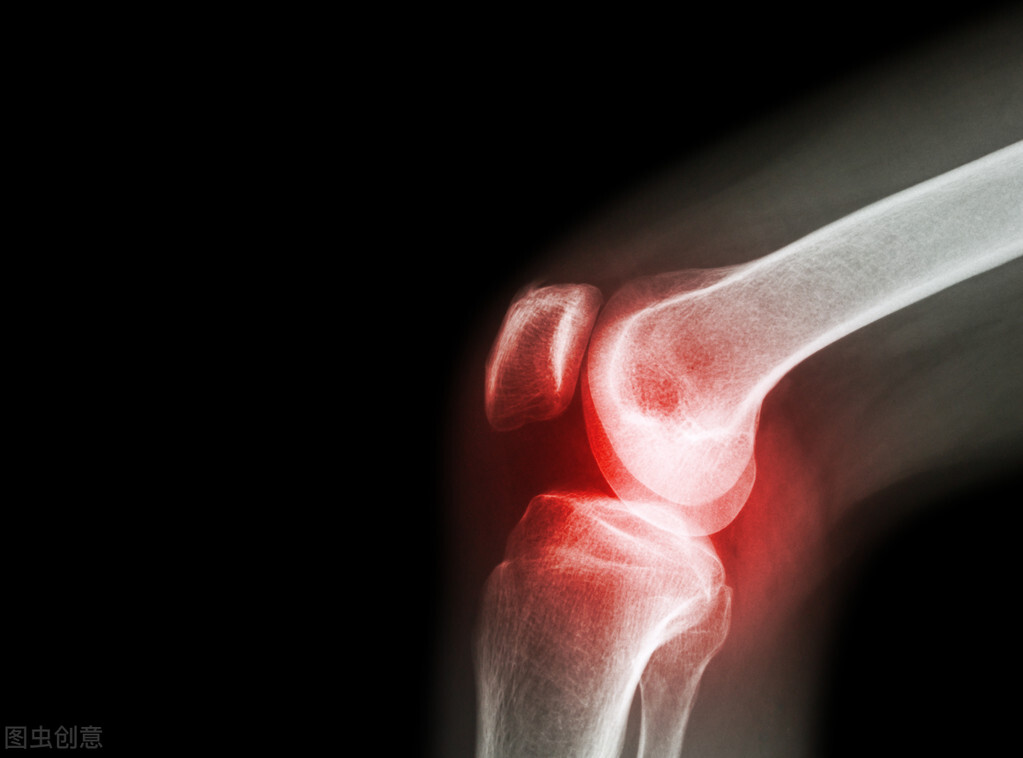

高尿酸血症患者出现尿酸盐结晶沉积,导致关节炎(痛风性关节炎)、尿酸性肾病和肾结石称为痛风,也有学者仅将痛风性关节炎称为痛风。

若无症状高尿酸血症患者,关节超声、双能CT或X线发现尿酸钠晶体沉积和/或痛风性骨侵蚀,可诊断为亚临床痛风。

(3)痛风中期:此期痛风性关节炎由于反复急性发作造成的损伤,使关节出现不同程度的骨破坏与功能障碍,形成慢性痛风性关节炎。可出现皮下痛风石,也可有尿酸性肾病及肾结石的形成,肾功能可正常或轻度减退。

(4)痛风晚期:出现明显的关节畸形及功能障碍,皮下痛风石数量增多、体积增大,可以破溃出白色尿盐结晶。尿酸性肾病及肾结石有所发展,肾功能明显减退,可出现氮质血症及尿毒症。

约50%病例第一跖趾关节为首发关节在整个病程中约90%以上病人均有第一跖趾关节受累称为足痛风。除跖趾关节外四肢关节均可受累但大多数为下肢关节越是肢体远端关节受累其症状也愈典型。关节受累的分布及其组成比有人综合国内报道879例依次为第一跖趾关节(58.7%)跗跖关节(11.7%)掌指和指间关节8.9%、踝关节(8.7%)、膝关节(3.9%)、腕关节(2.8%)其他关节少见。